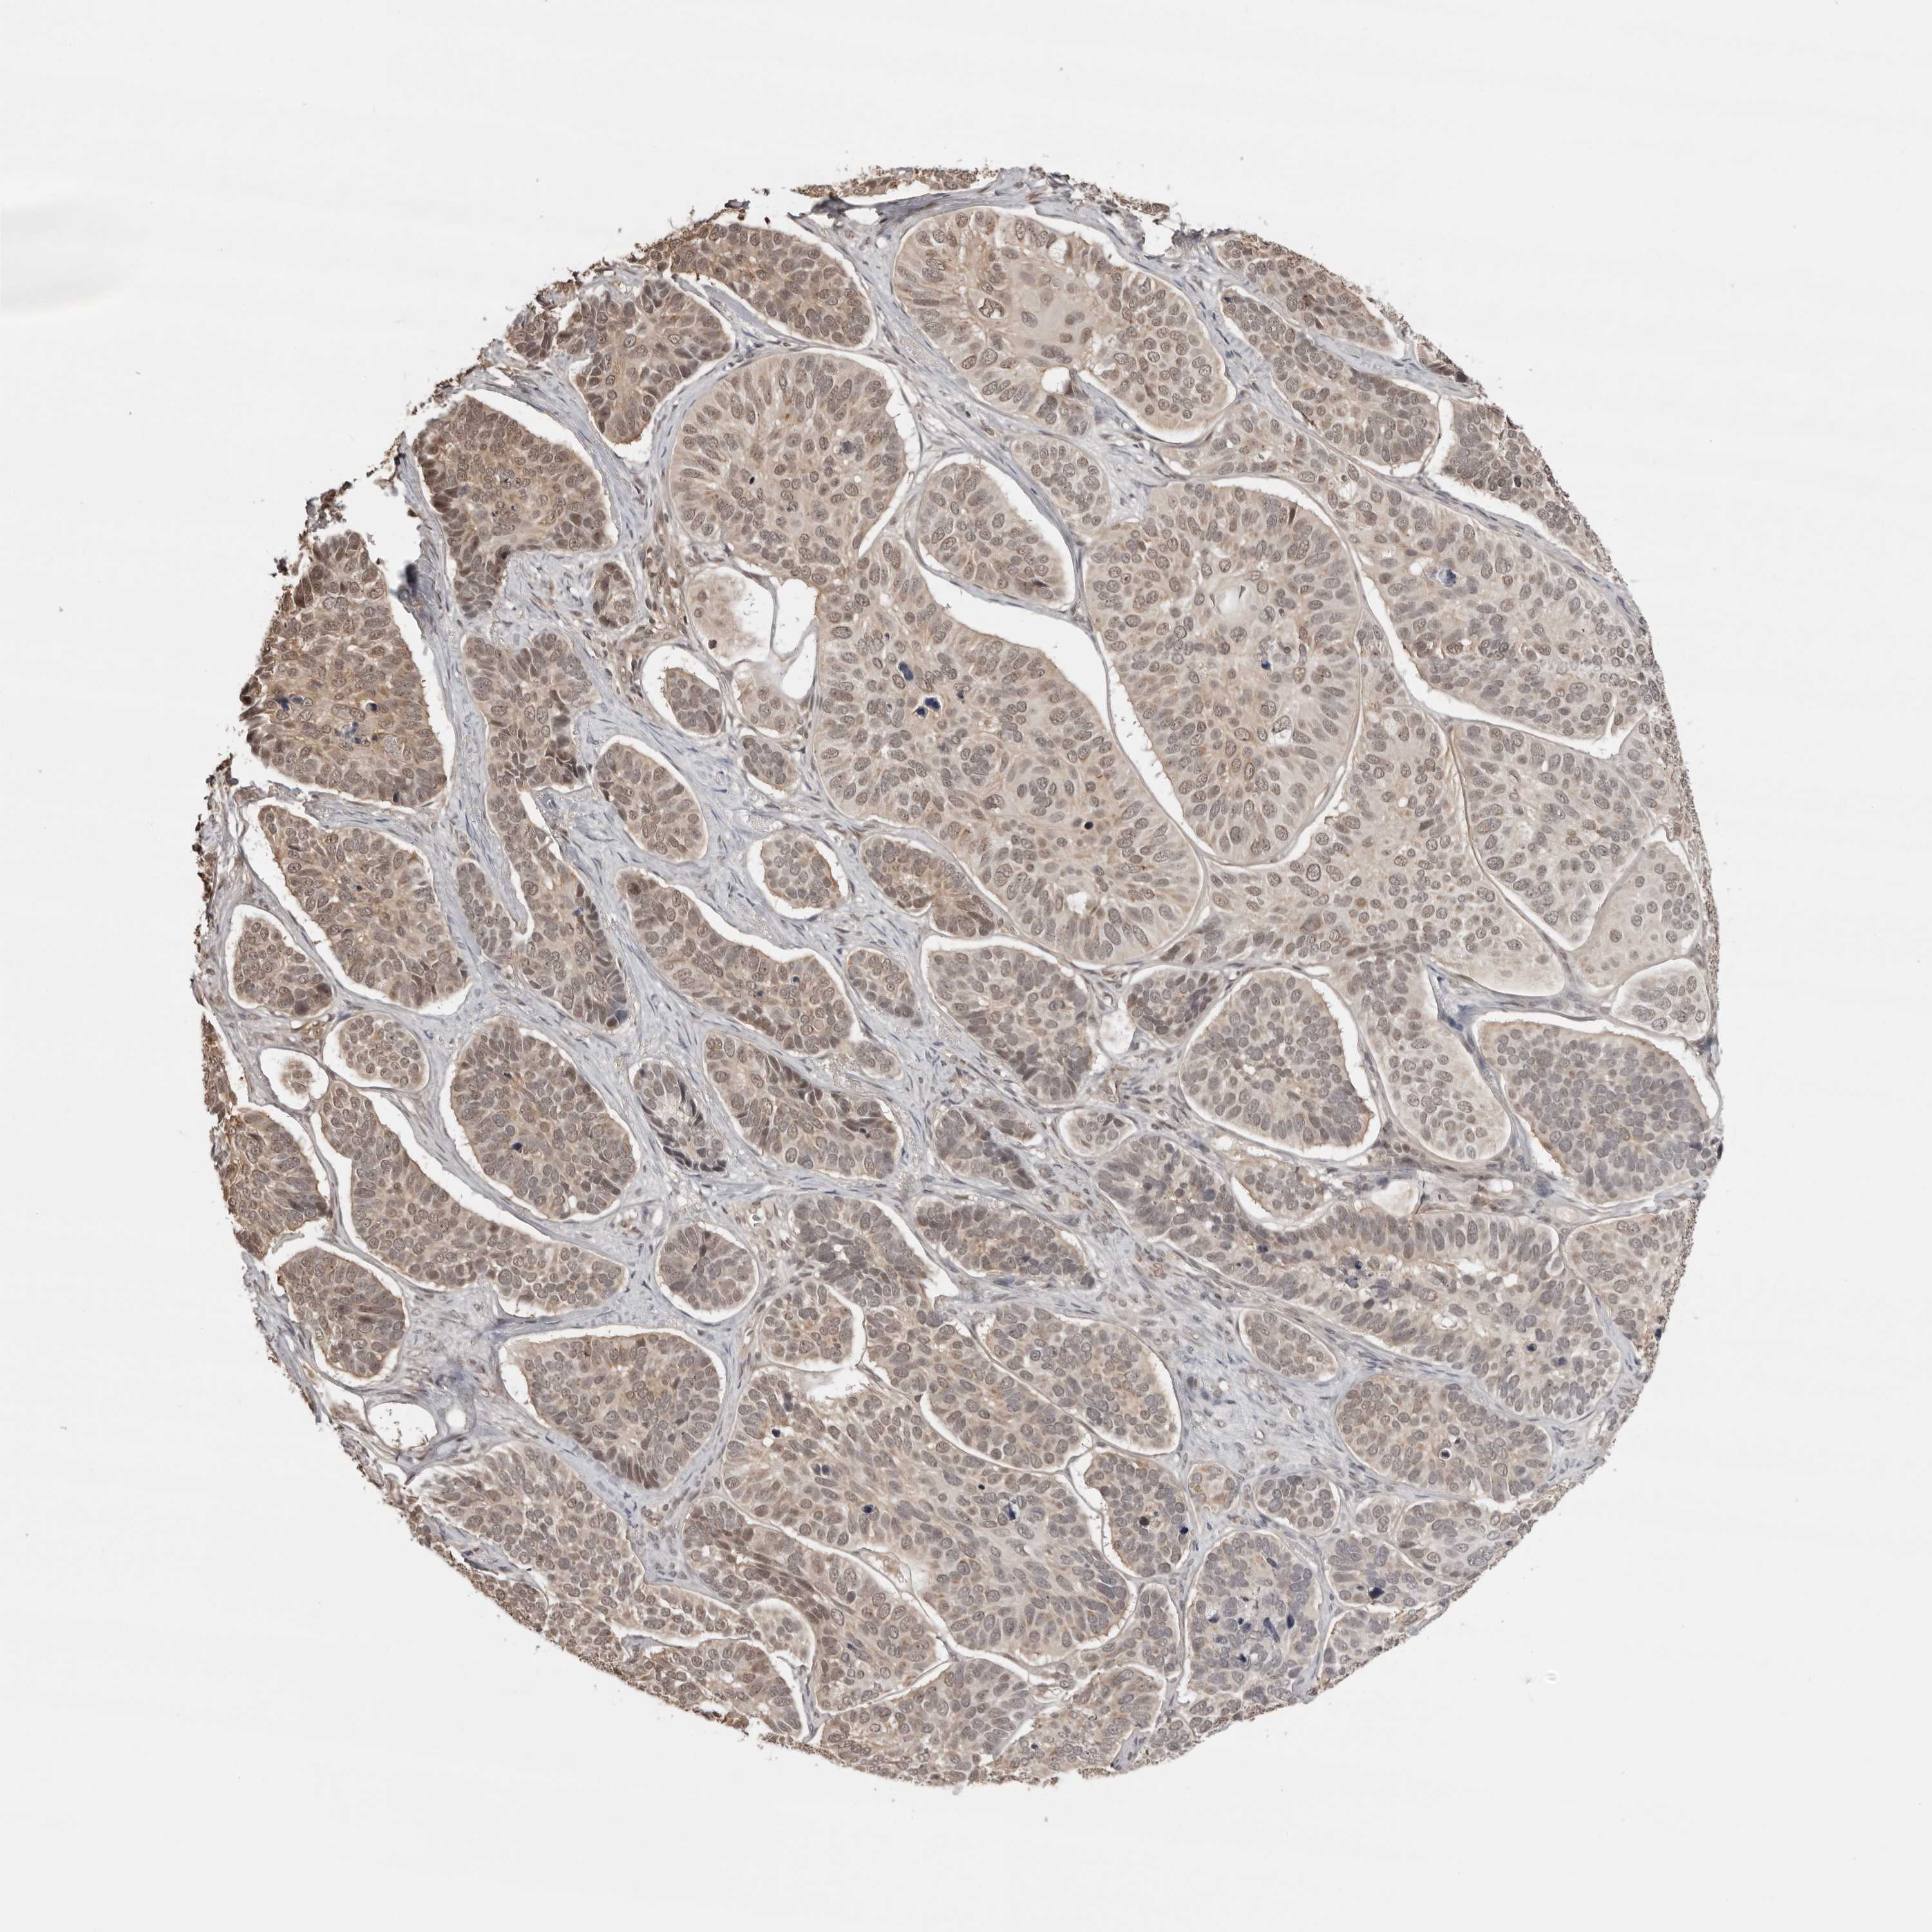

SKIN CANCER - Protein expressioni

A mouse-over function shows sample information and annotation data. Click on an image to view it in a full screen mode. Samples can be filtered based on level of antibody staining by selecting one or several of the following categories: high, medium, low and not detected. The assay and annotation is described here.

Each image is clickable and will lead to virtual microscopy that enables deeper exploration of all samples and also displays staining intensity scores, fraction scores and subcellular localization as well as patient and tissue information for each sample.

Antibody HPA031255

Staining

High

Medium

Low

Not detected

Intensity

Strong

Moderate

Weak

Negative

Quantity

>75%

75%-25%

<25%

None

Location

Nuclear

Cytoplasmic/membranous

Cytoplasmic/membranous,nuclear

Squamous cell carcinoma, NOS